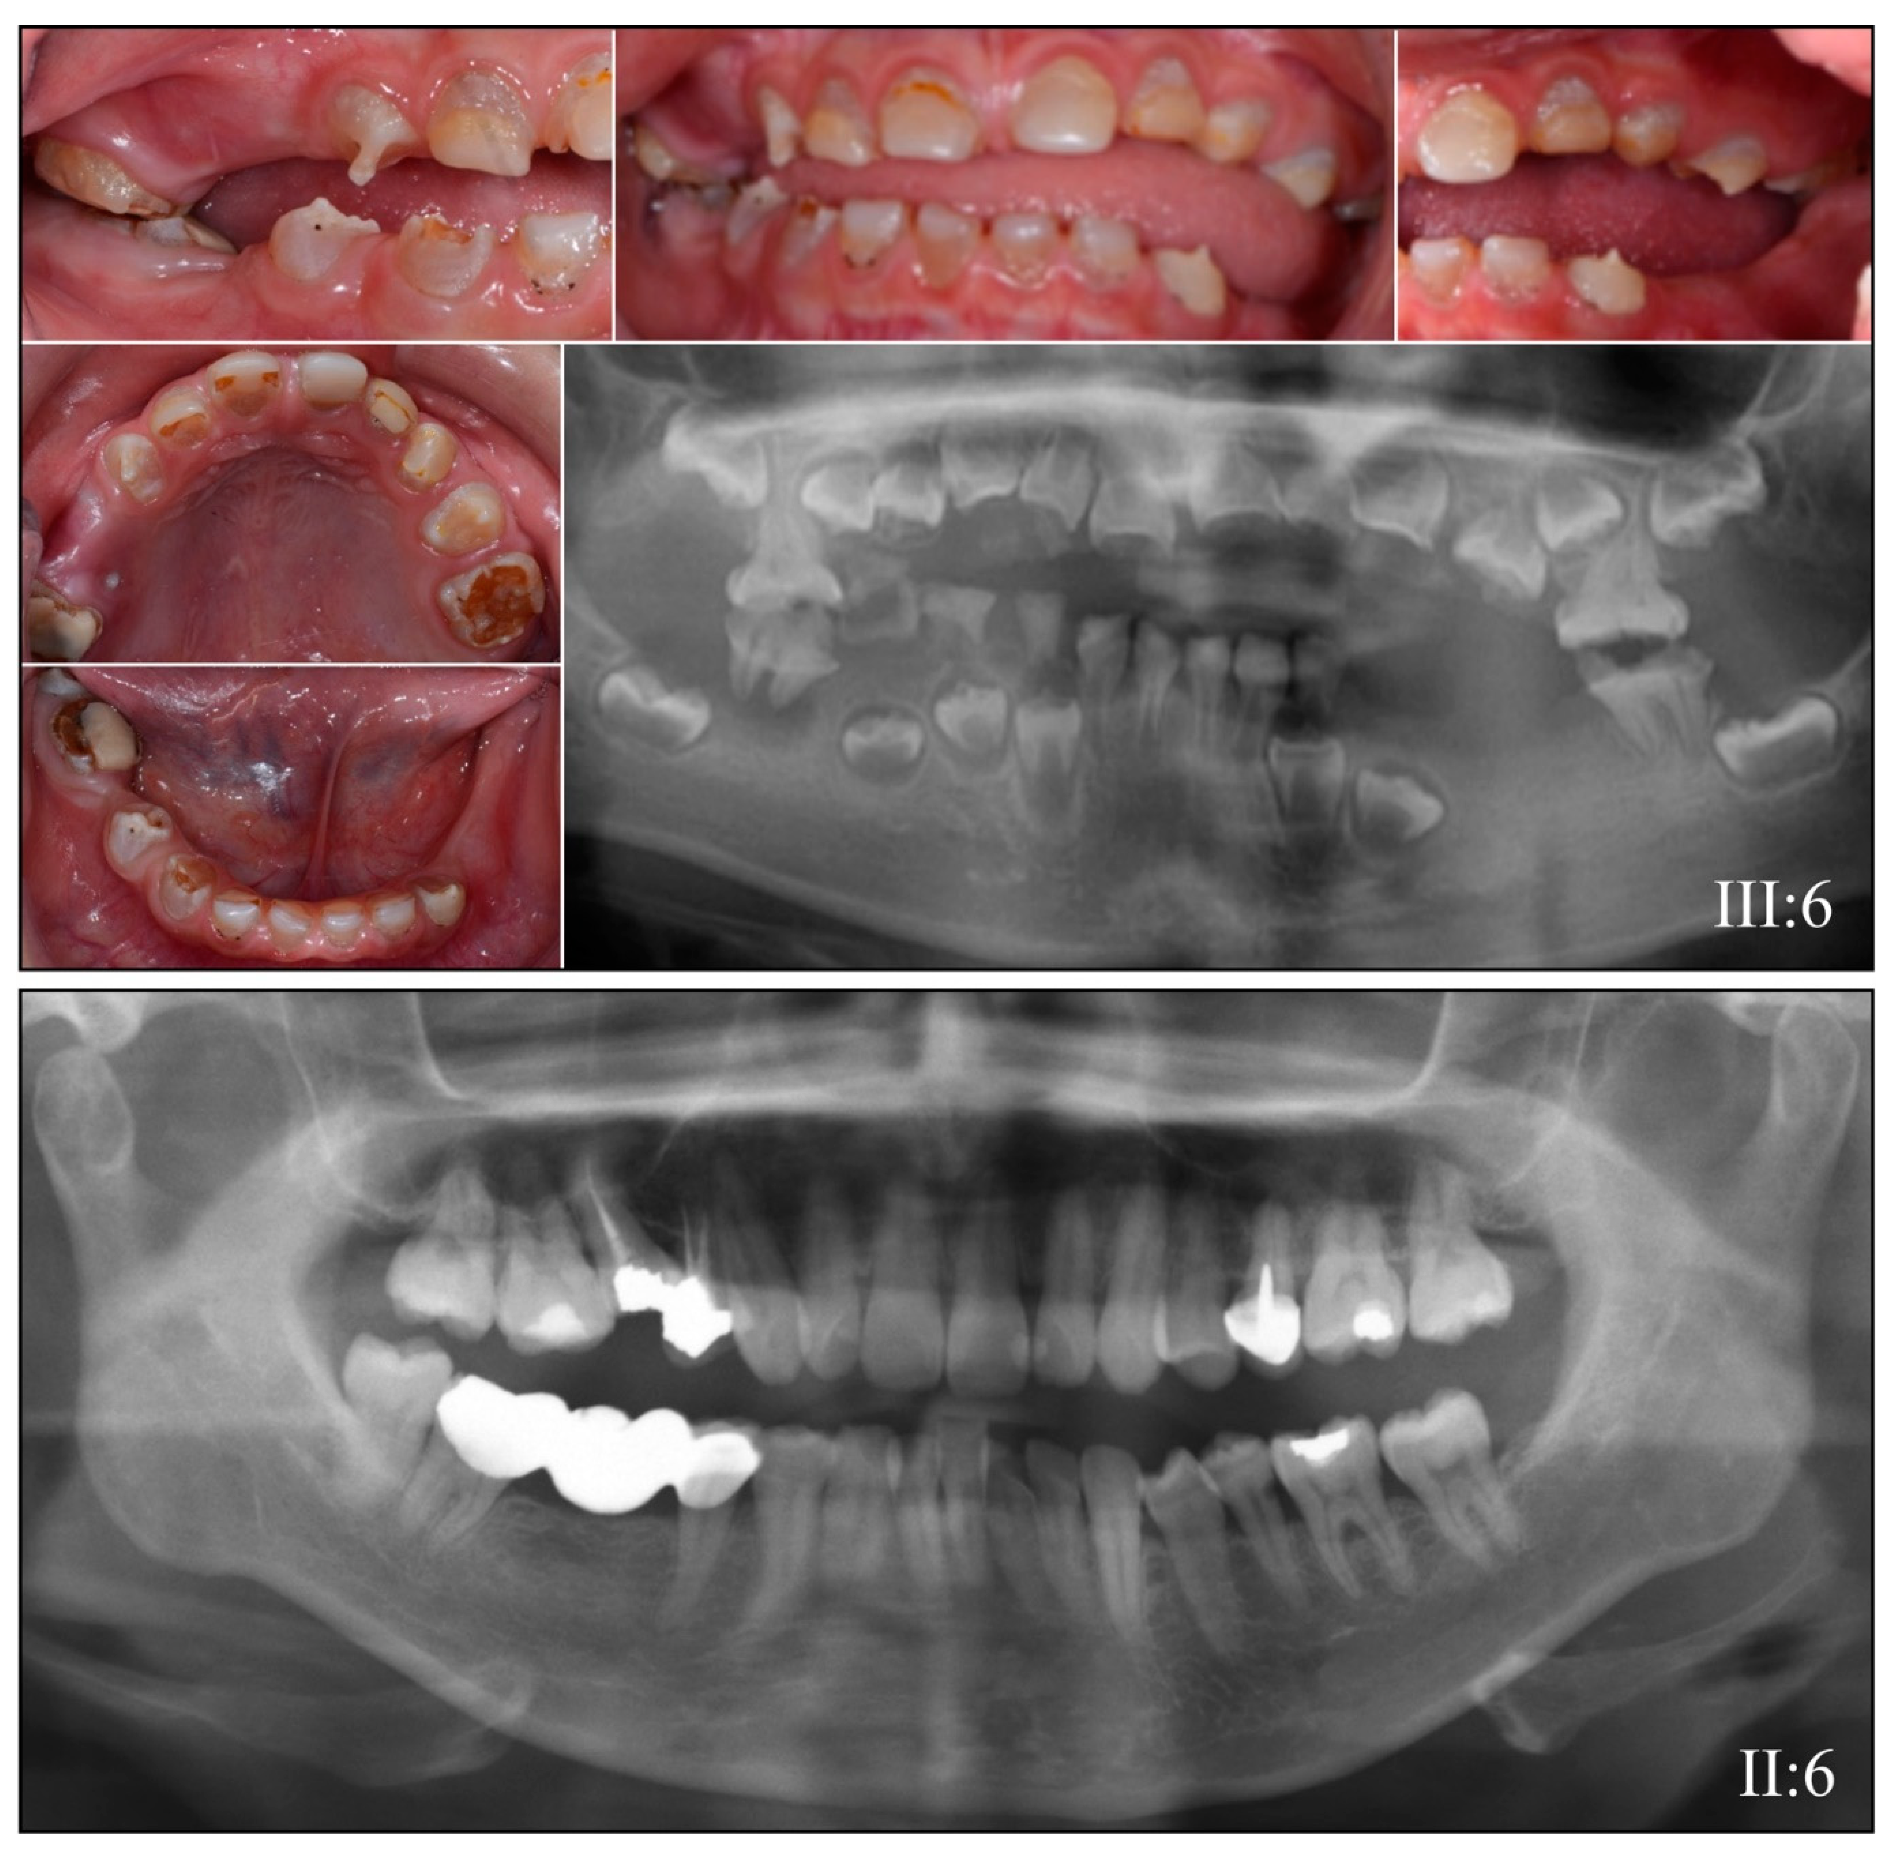

3.2. Four Families with DGI-III: 5′ DSPP Mutations

| 1 | Illumina HiSeq 2500 (WES) | NG_011595.1:g.7430C>T; NM_014208.3:c.50C>T; NP_055023.2:p.(Pro17Leu) | Missense | II:6, unaffected mother: 136.75× III:5, affected 1st child: 159.3× III:6, affected 2nd child: 129.86× |